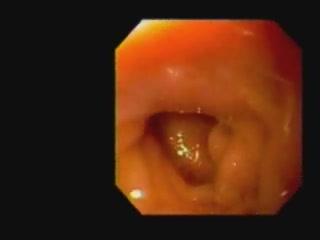

Endoscopic Placement and Fix..

Endoscopic Placement and Fix..

Jeffrey M. Marks, MD,FACS; Amitabh Chak, MD; Victor Chen, MD; Jeffrey Ponsky, MD, FACS / CINE-MED